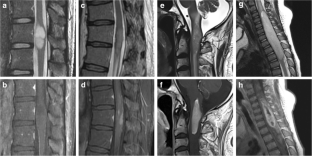

Diffuse midline glioma with histone H3 K27M mutation is a new entity described in the 2016 update of the World Health Organization Classification of Tumors of the Central Nervous System. The purpose of this study was to evaluate the clinical and imaging characteristics to predict the presence of H3 K27M mutation in spinal cord glioma using a machine learning–based classification model.

A total of 41 spinal cord glioma patients consisting of 24 H3 K27M mutants and 17 wild types were enrolled in this retrospective study. A total of 17 clinical and radiological features were evaluated. The random forest (RF) model was trained with the clinical and radiological features to predict the presence of H3 K27M mutation. The diagnostic ability of the RF model was evaluated using receiver operating characteristic (ROC) analysis. Area under the ROC curves (AUC) was calculated.

MR imaging features of spinal cord diffuse midline gliomas were heterogeneous. Hemorrhage was the only variable that was able to differentiate H3 K27M mutated tumors from wild-type tumors in univariate analysis (p = 0.033). RF classifier yielded 0.632 classification AUC (95% CI, 0.456–0.808), 63.4% accuracy, 45.8% sensitivity, and 88.2% specificity.

Our findings indicate that clinical and radiological features are associated with H3 K27M mutation status in spinal cord glioma.